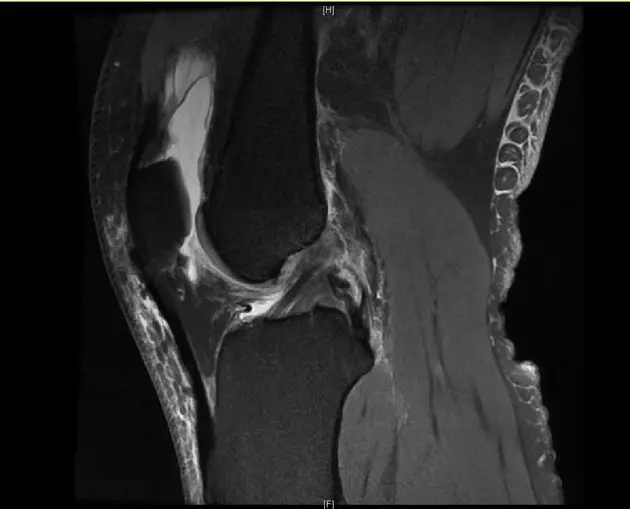

后交叉韧带断裂

这个病例韧带连续性中断松弛,尤其上止点的信号增高;从这个层面来看它的上止点形态不完整,部分信号增高;从这个层面可以看到,韧带的形态信号增粗,松弛,信号也是增高的,所以这个病例可以诊断为后交叉韧带断裂。